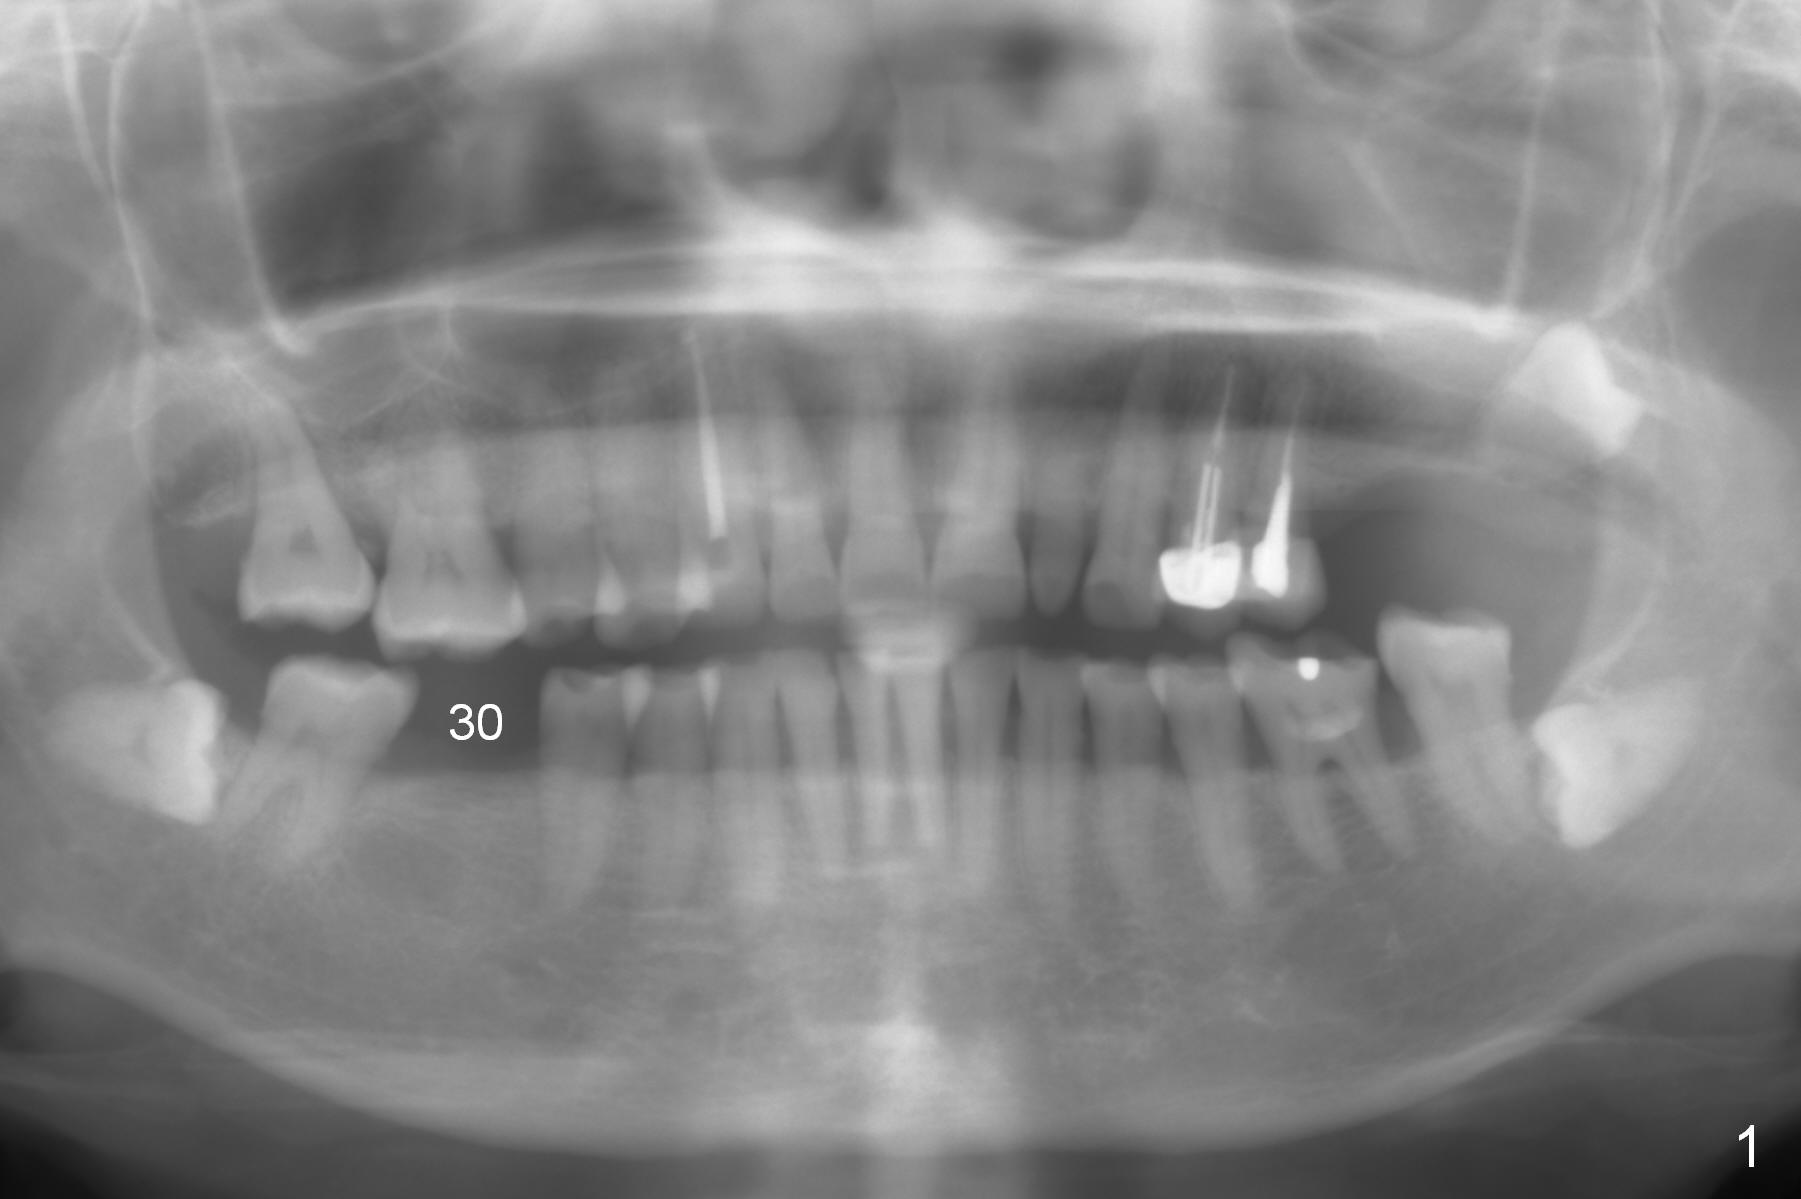

A 57-year-old woman has 3 missing molars, including #30 (Fig.1). Although she looks skinny, clinically the ridge is moderately wide. Magic Split will be used for access (flapless) and bone density testing. From PA, the bone density does not seem to be low (Fig.2). Use the 1.6 mm drill without stopper for further bone density testing. The initial depth will be 15 mm (gingival level, Fig.3). After PA confirmation of the trajectory, use 3.8 mm Magic Drill for 15 mm. Try 4.5x11 mm dummy implant, followed by PA. When an abutment is placed, trim the opposing surpraerupted tooth if necessary (Fig.3 arrow).